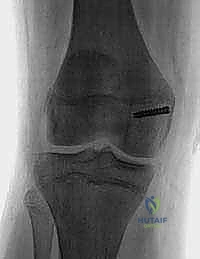

- Plain Radiographs:

- AP, Lateral, Sunrise/Merchant Views: Essential. The sunrise view, requiring 30-45 degrees of flexion, might be delayed due to acute pain but is crucial for assessing trochlear morphology and patellar tilt.

- Limitations: Plain films can miss up to 40% of arthroscopically documented chondral or osteochondral lesions. Subtle slivers of bone can be easily overlooked.